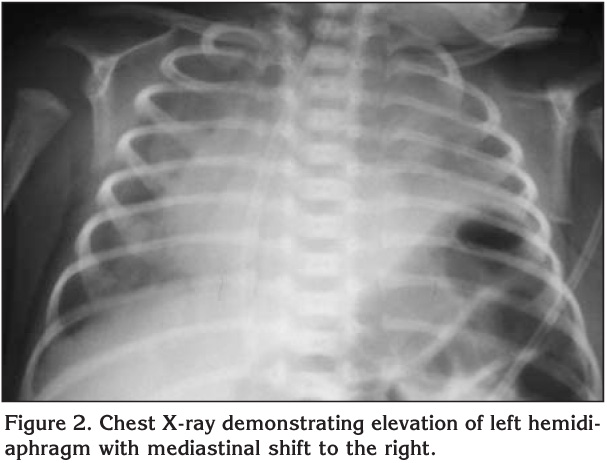

Diaphragmatic Paralysis - Symptoms, Evaluation, Therapy ...

Diaphragmatic Paralysis - Symptoms, Evaluation, Therapy and Outcome Issahar Ben-Dov The right phrenic nerve follows the superior vena cava and the right side of nerve damage during cardiothoracic surgery or cannulation of central veins ... Doc Viewer